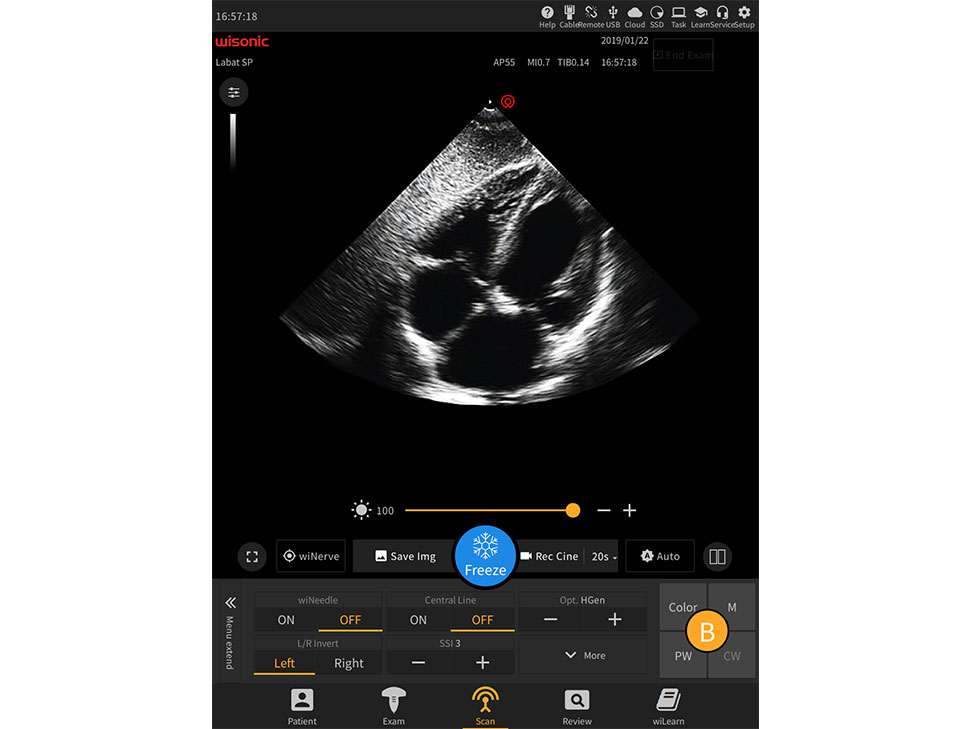

Overview

21.3

-inch Large Touch Screen Display

Anti-glare, full size, high sensitivity

Simplified Control Panel

La pantalla táctil completa más grande de la industria

Apoyo Desinfección Líquida

Operación multitáctil

Panel mínimo para personalización clínica

Trackball impermeable de alta sensibilidad

Anti-salpicaduras

Joystick multifunción